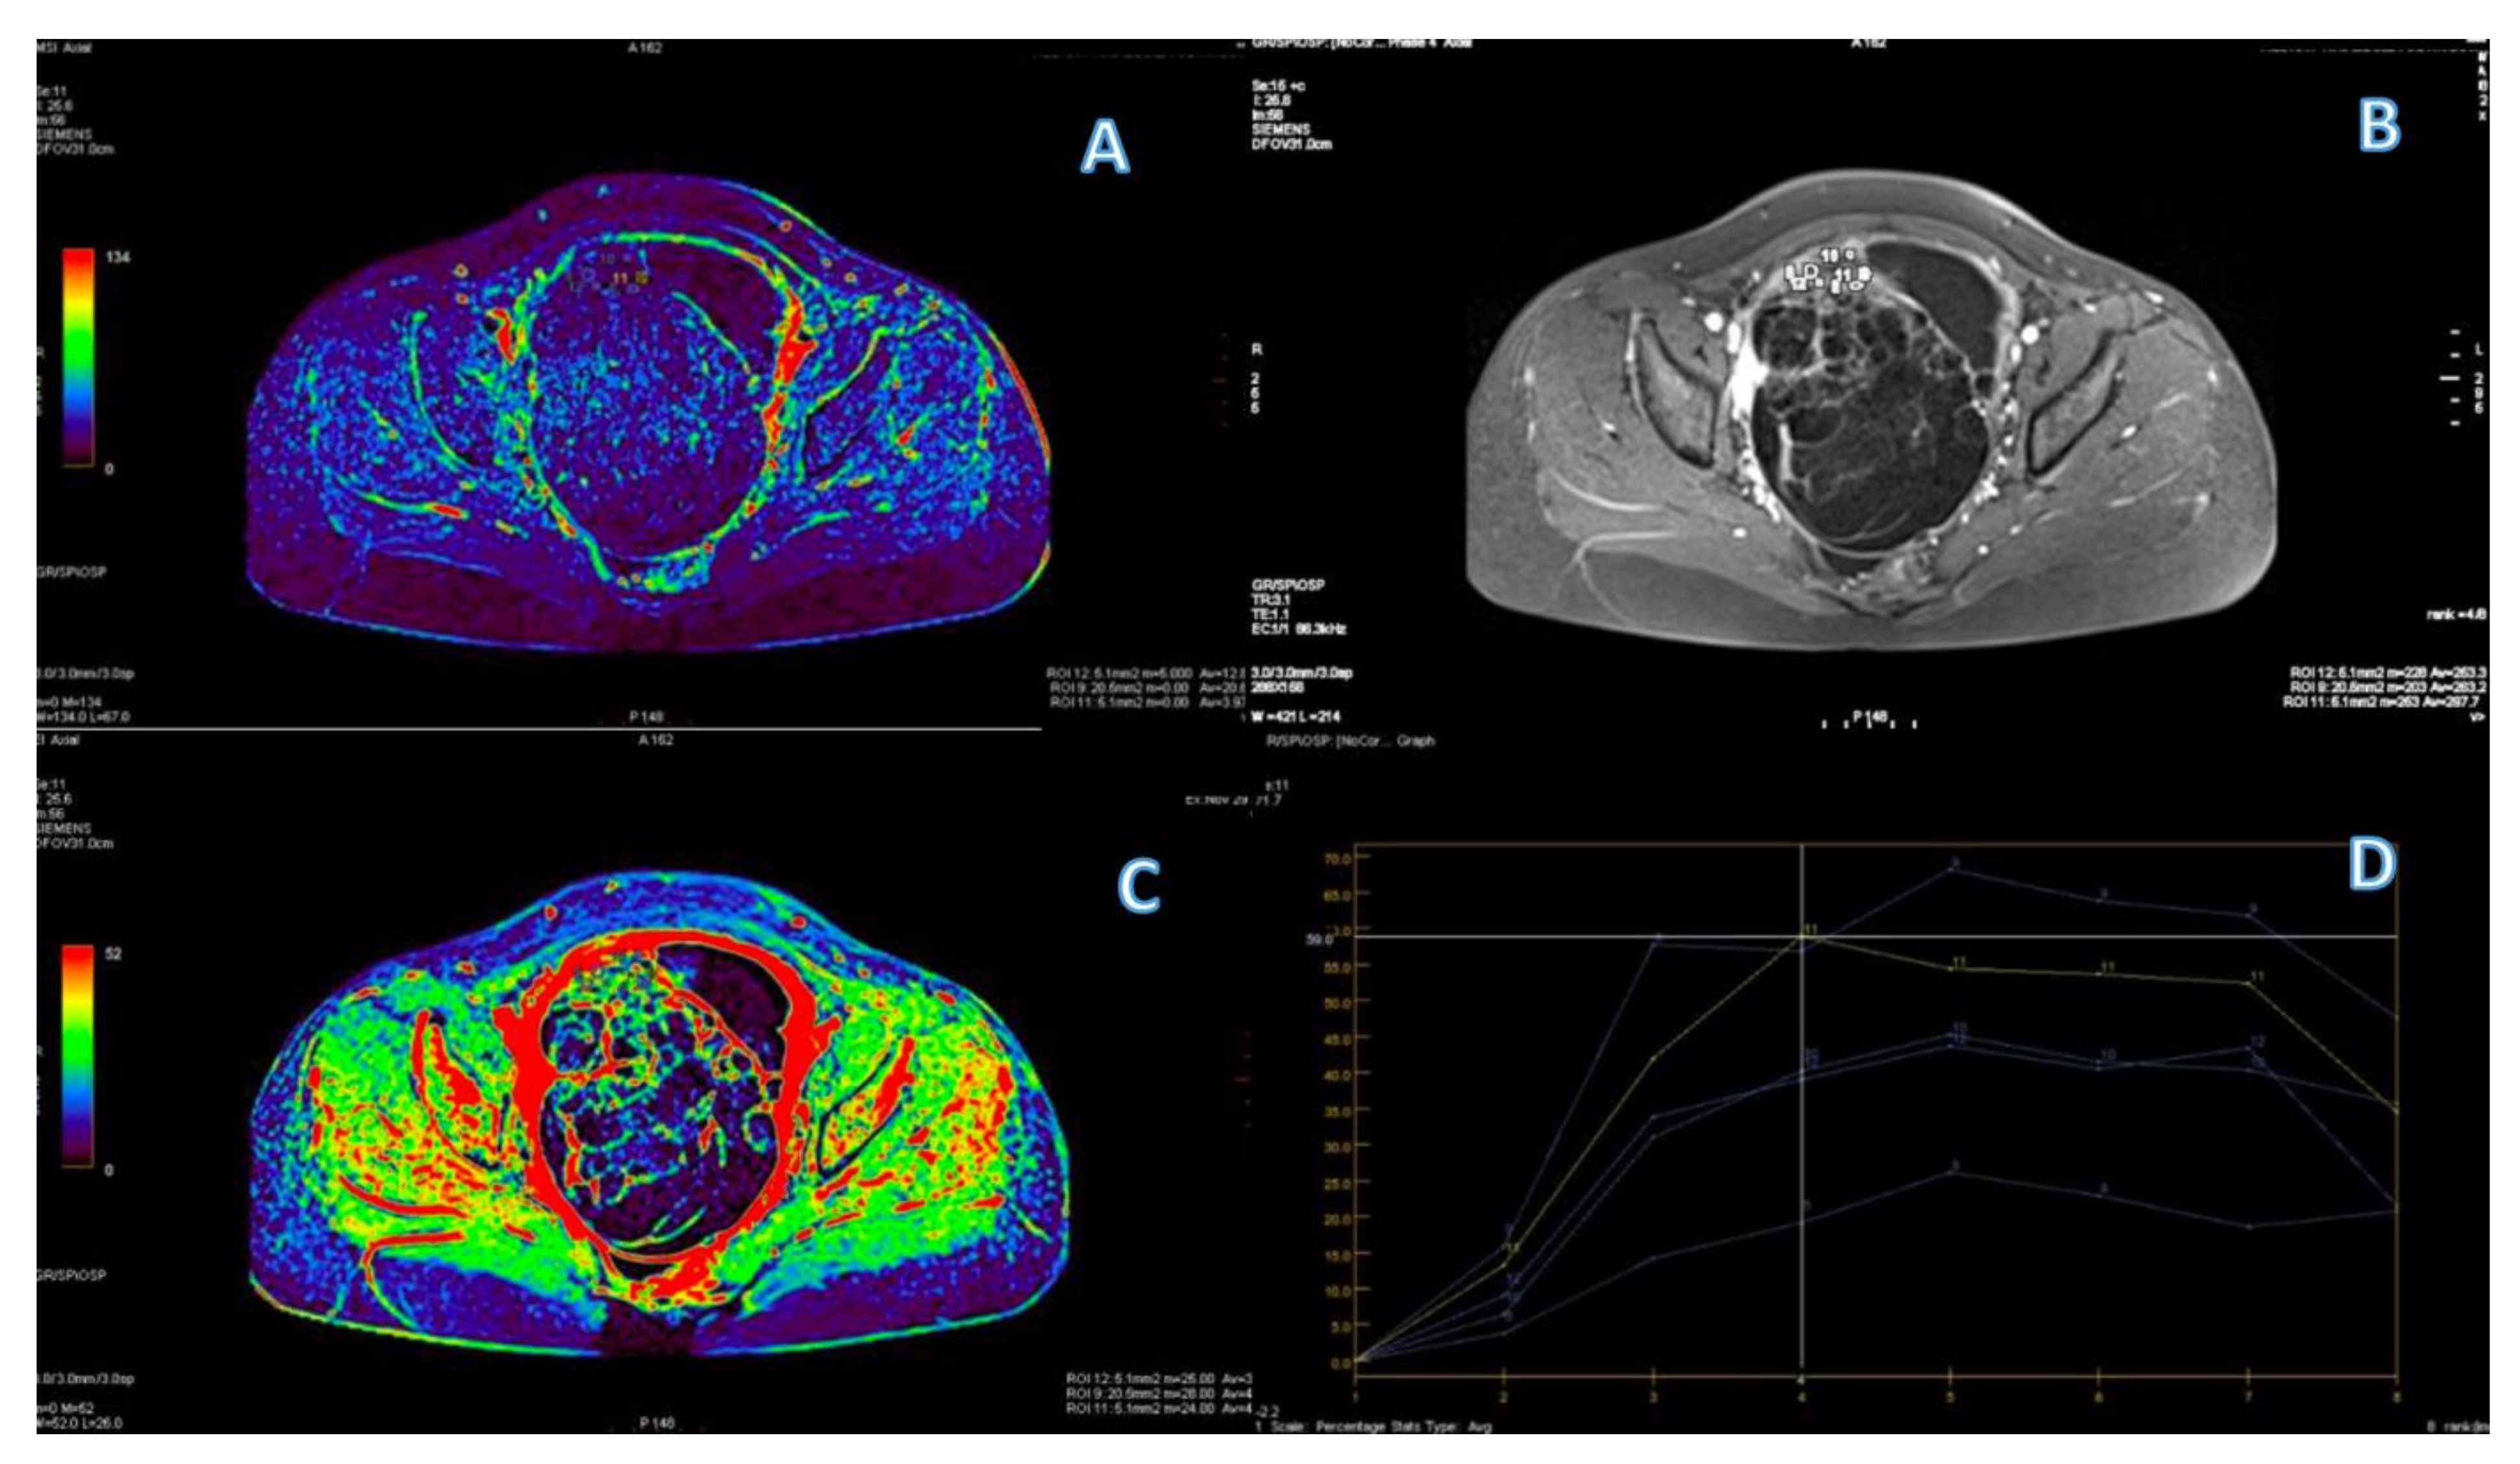

3.4. ROC Curve for LGSC vs. MOC